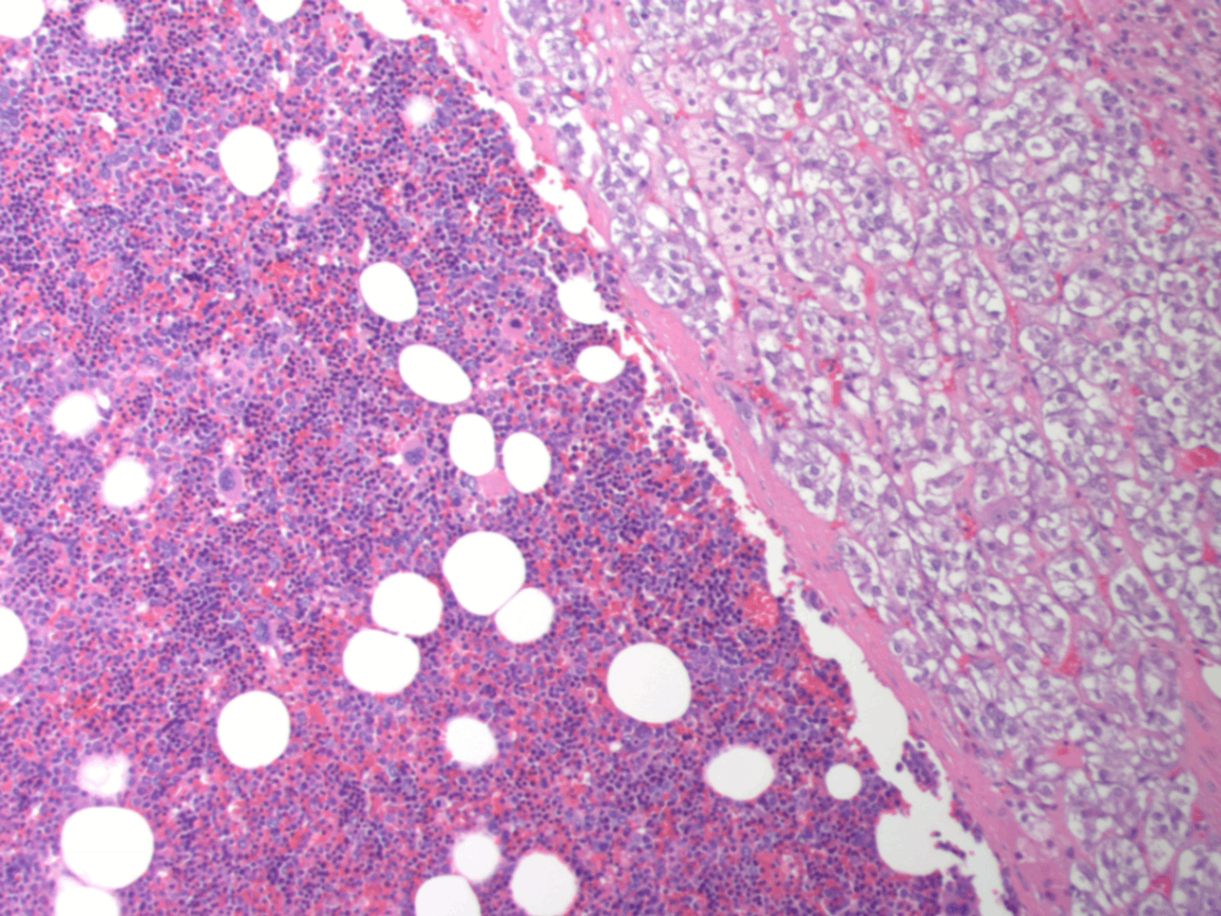

2. 부신골수지방종 (adrenal myelolipoma)

• 흔치 않지만 양성인 종양

성숙한 지방세포와 조혈세포로 구성됨

• 대부분 우연히 발견되는 incidentaloma

• 드물게 매우 큰 크기로 성장할 수 있음

Adrenal myelolipoma, Wikipedia Commons